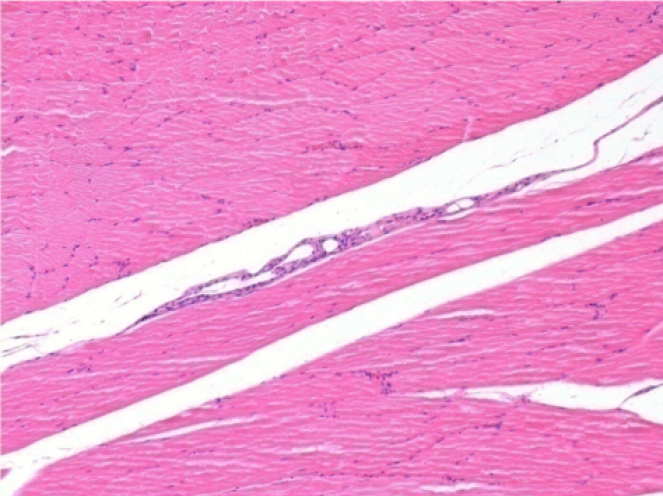

7 місяців (210 днів) після ін'єкції 0,1 мл Ендопіл в правий претибіальний м'яз.

Повна Restitutio ad integrum через 7 місяців

Л :Контроль 50x210 днів

П:50X-210 днів